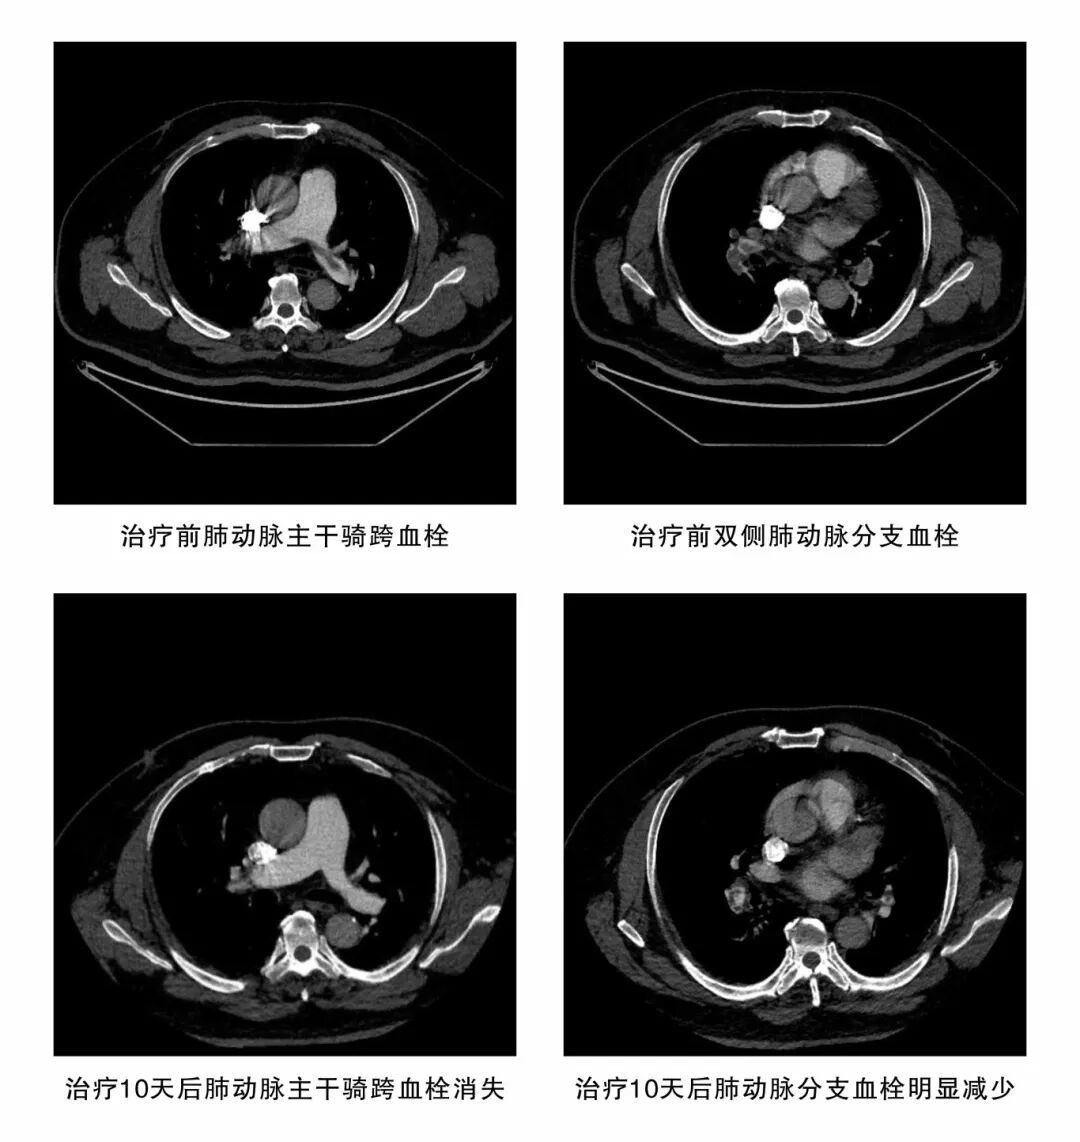

11月1日,一名50多岁的男性患者因“突发心慌、气喘2天”被紧急转入潜江市中心医院。急诊团队迅速识别病情并立即开启绿色通道。检查结果令人震惊:血液D-二聚体飙升至6.61mg/L(远超正常标准),强烈提示血栓形成;肺动脉 CTA 影像更令人揪心——双肺肺动脉从主干到分支布满多发栓塞,最大栓子体积达 22.78cm³,右心室已明显扩大。患者病情异常凶险,如同肺部布满“炸弹”,随时可能引爆,造成呼吸循环衰竭,导致猝死。

功夫不负有心人。在医护团队的精心治疗与细心守护下,患者的病情一天天好转。11月11日复查肺动脉CT影像传来捷报,患者肺部血栓已明显吸收;11月19日,患者自觉胸闷、气喘症状已显著缓解。当停用肝素的那一刻,整个医护团队悬着的心终于落下。